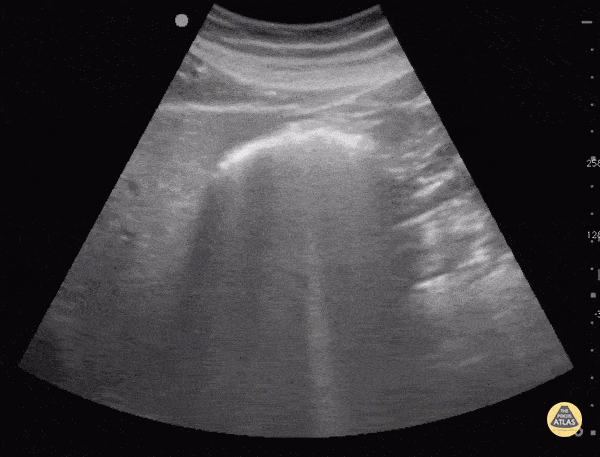

Bowel-GI - Bowel Gas

Bowel gas scatters ultrasound waves making the structure containing the gas as well as posterior structures difficult to visualize. Applying more gentle graded pressure to the probe may displace the gas and improve visualization. Sukh Singh, MD